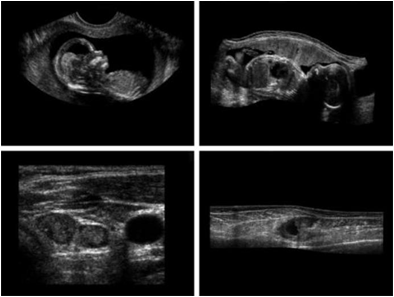

초음파: 1~5MHz 이하. 의료진단

a)아기1 b)아기2 c)갑상선 d)손상된근육